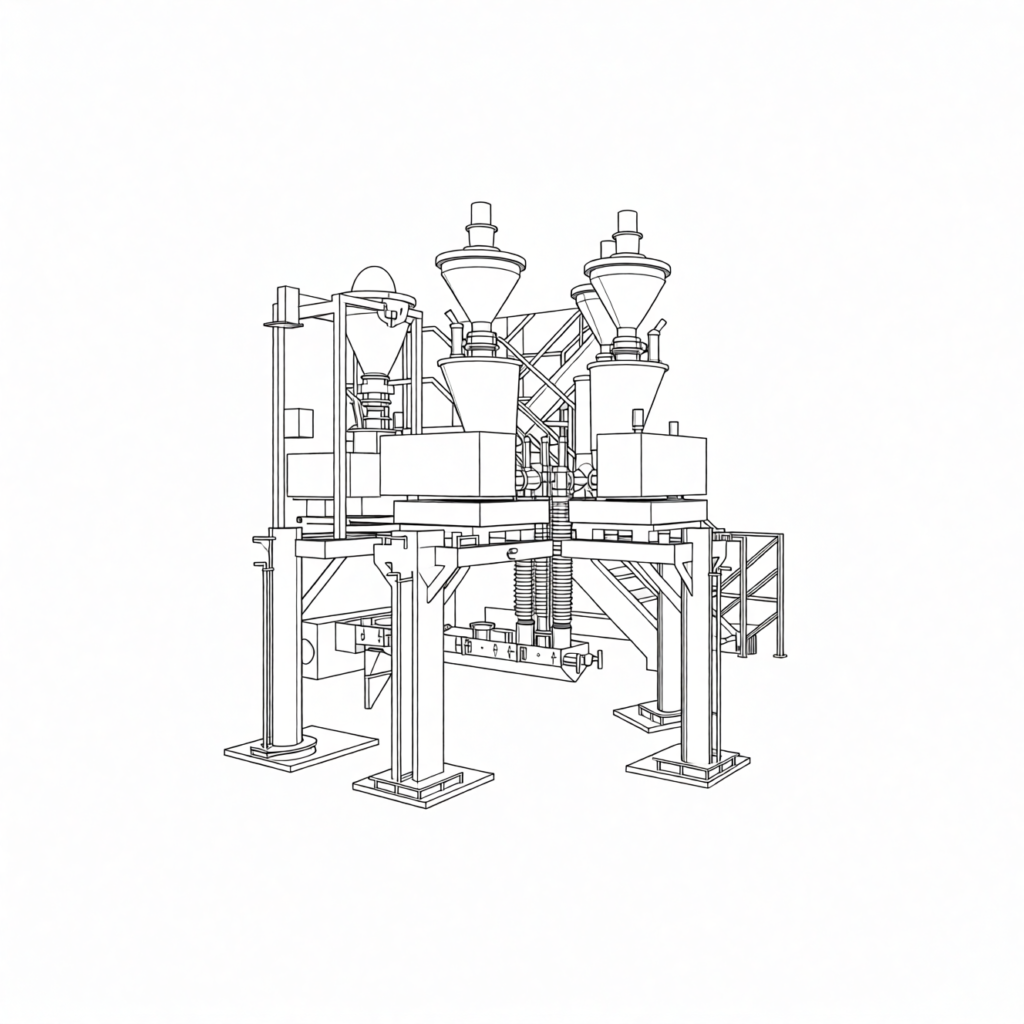

Fabricación en Contínuo

iXOLAB apuesta por la fabricación en continuo que representa una transformación paradigmática en la industria farmacéutica, sustituyendo la producción por lotes por un flujo ininterrumpido de materiales a través de todas las etapas: dosificación precisa, mezcla, granulación, compresión y recubrimiento operan de forma integrada y sincronizada.

Este modelo reduce drásticamente los tiempos —de días a minutos—, minimiza la huella física de las instalaciones y elimina inventarios intermedios. Su principal ventaja radica en el control de calidad en tiempo real mediante tecnologías analíticas de proceso (PAT).

La flexibilidad inherente facilita la producción ágil de volúmenes ajustados, beneficiando ensayos clínicos y medicamentos de nicho. Como columna vertebral de la farmacia 4.0, la fabricación continua habilita la integración de inteligencia artificial para optimización autónoma y trazabilidad completa, sentando las bases para una producción personalizada a escala.